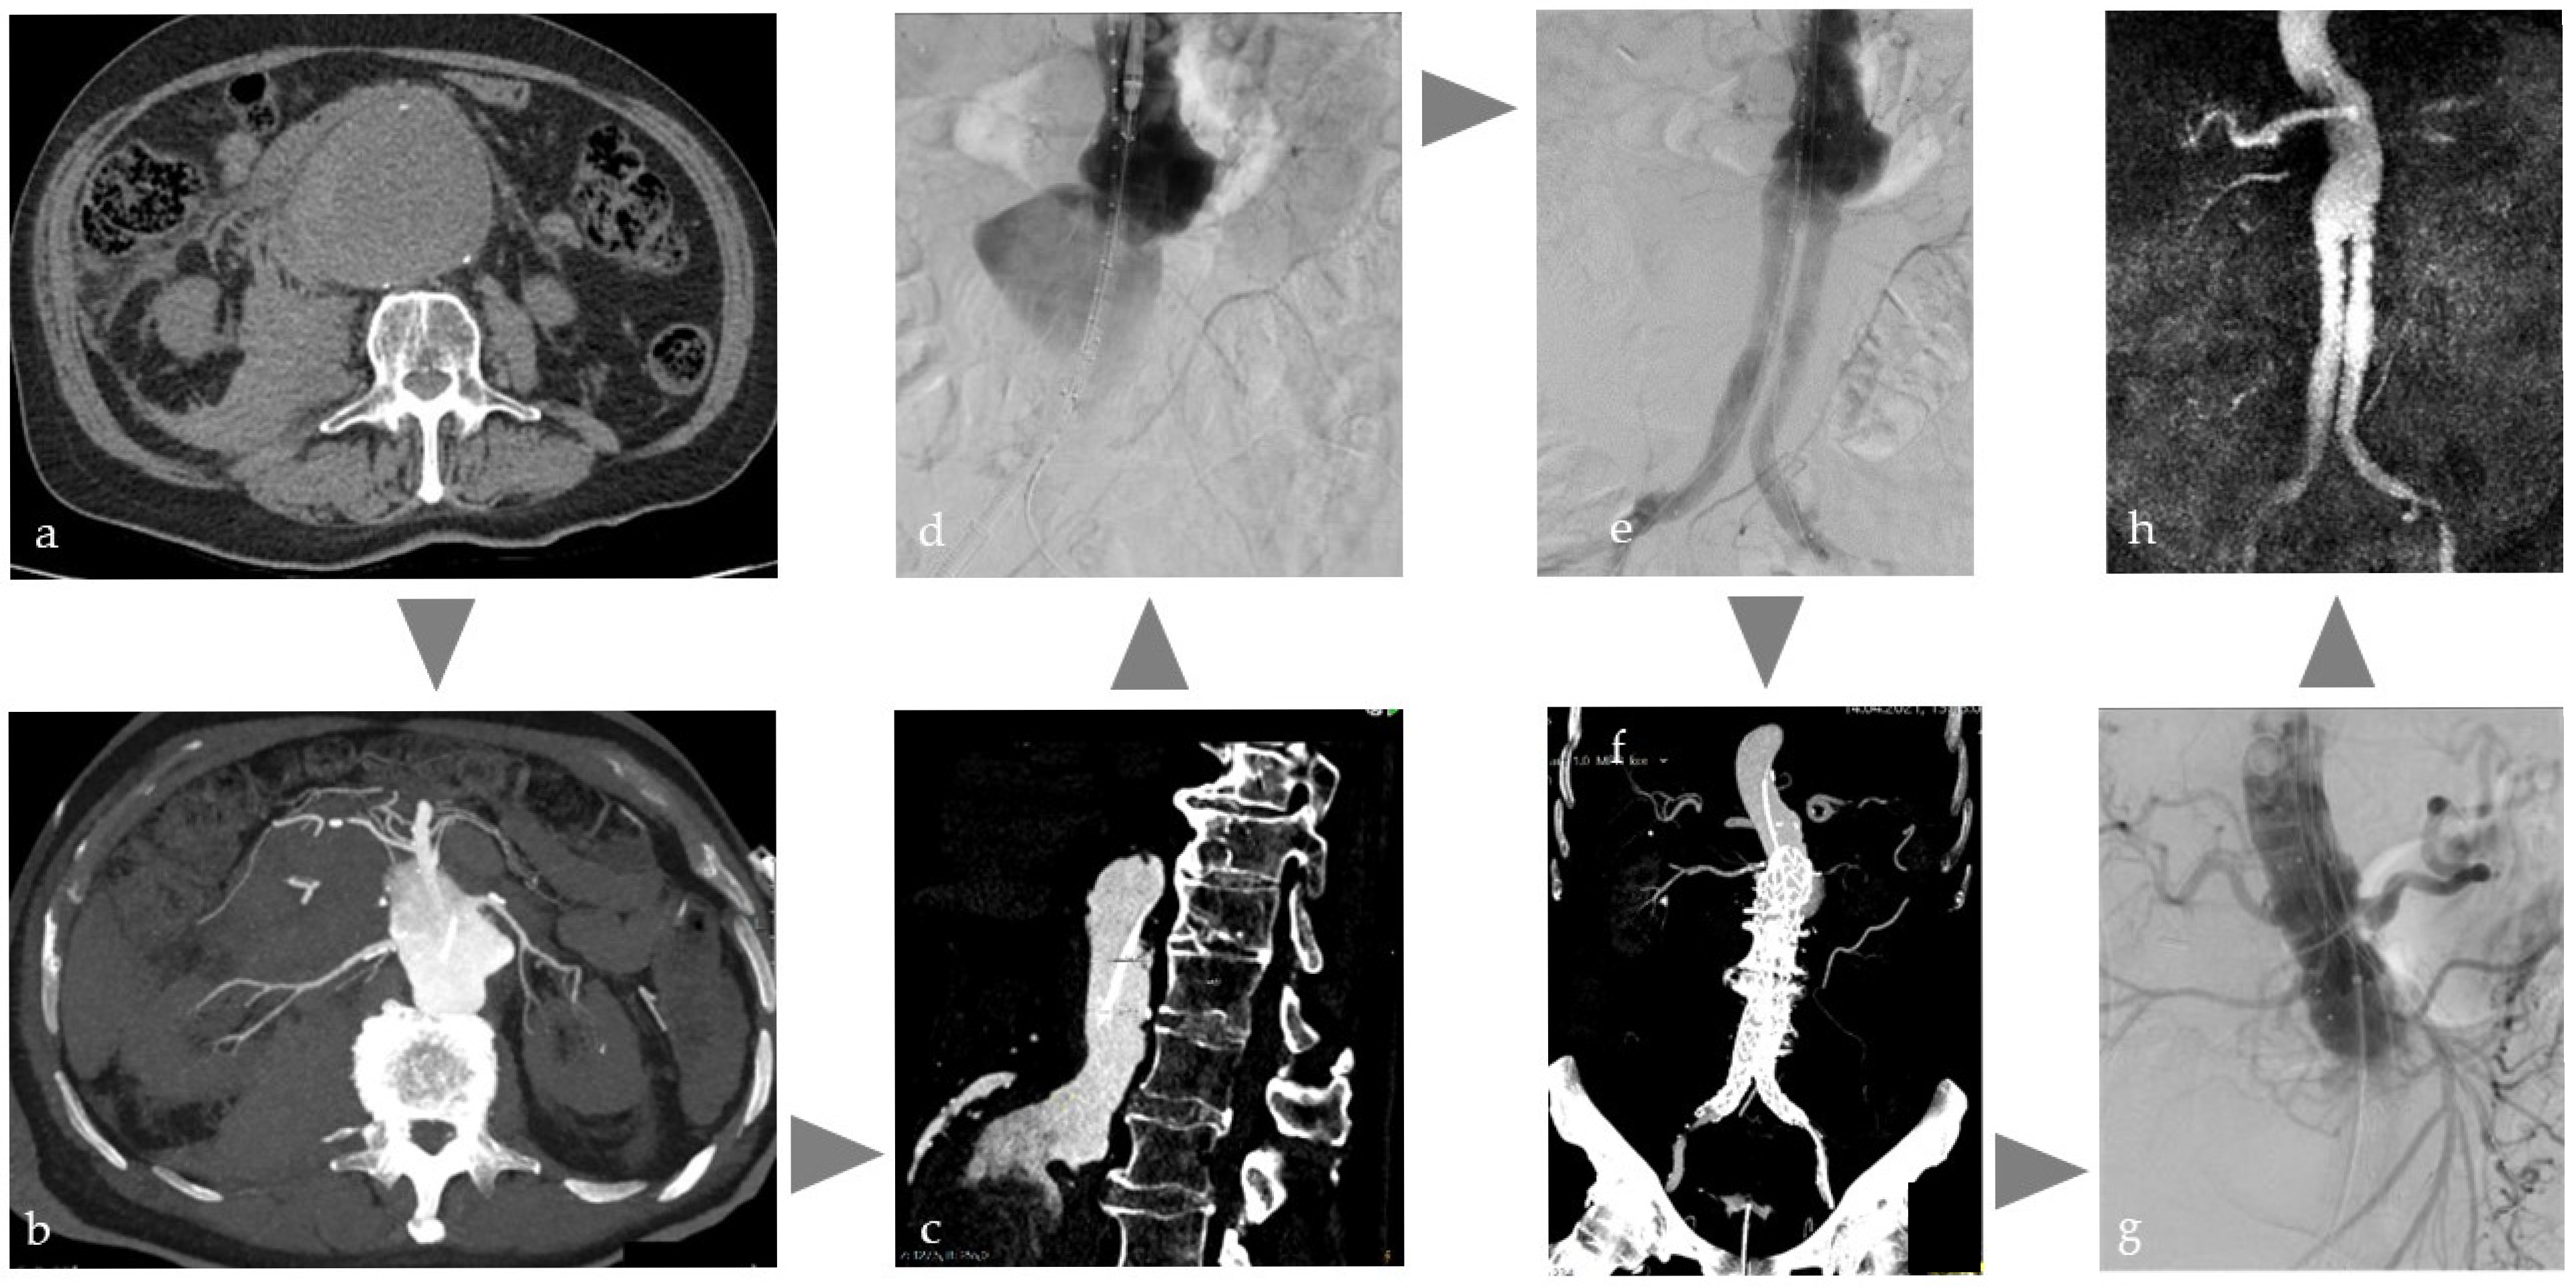

Figure 1. Illustration of the workflow of a combined intervention with percutaneous CT-guided biopsy and immediate transarterial chemoembolization of a cholangiocellular carcinoma in the left lobe of the liver in a patient on anticoagulation due to atrial fibrillation. (a) planning MRI (T1w late phase after liver-specific contrast agent) with tumor in the left lobe of the liver, (b) native planning CT with weakly hypodense tumor, (c) needle puncture with single slice CT and intra-aortic CM injection (15 mL volume with 1:10 dilution corresponding to about 1.5 mL BM), (d) DSA with super-selective probing of the feeders to segment 2 and placed needle to perform embolization directly after biopsy to avoid bleeding, (e) single slice CT image after lipiodol embolization of the tumor with no evidence of active bleeding.